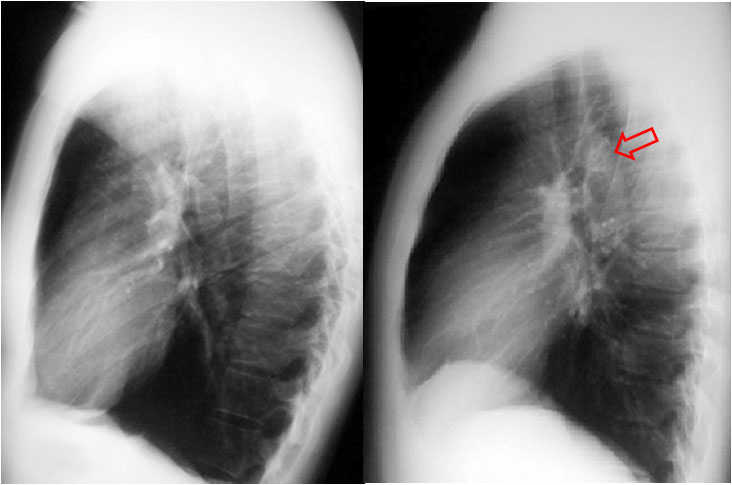

Signo de crecimiento del ventrículo izquierdo en la radiografía lateral de tórax. Consiste en un aumento de la distancia entre la vena cava inferior y el borde cardíaco posterior, mayor de 2 centímetros.

En la imagen vemos el signo en un paciente con insuficiencia aórtica. La flecha roja indica el borde cardíaco posterior y la flecha negra señala la entrada de la vena cava inferior.